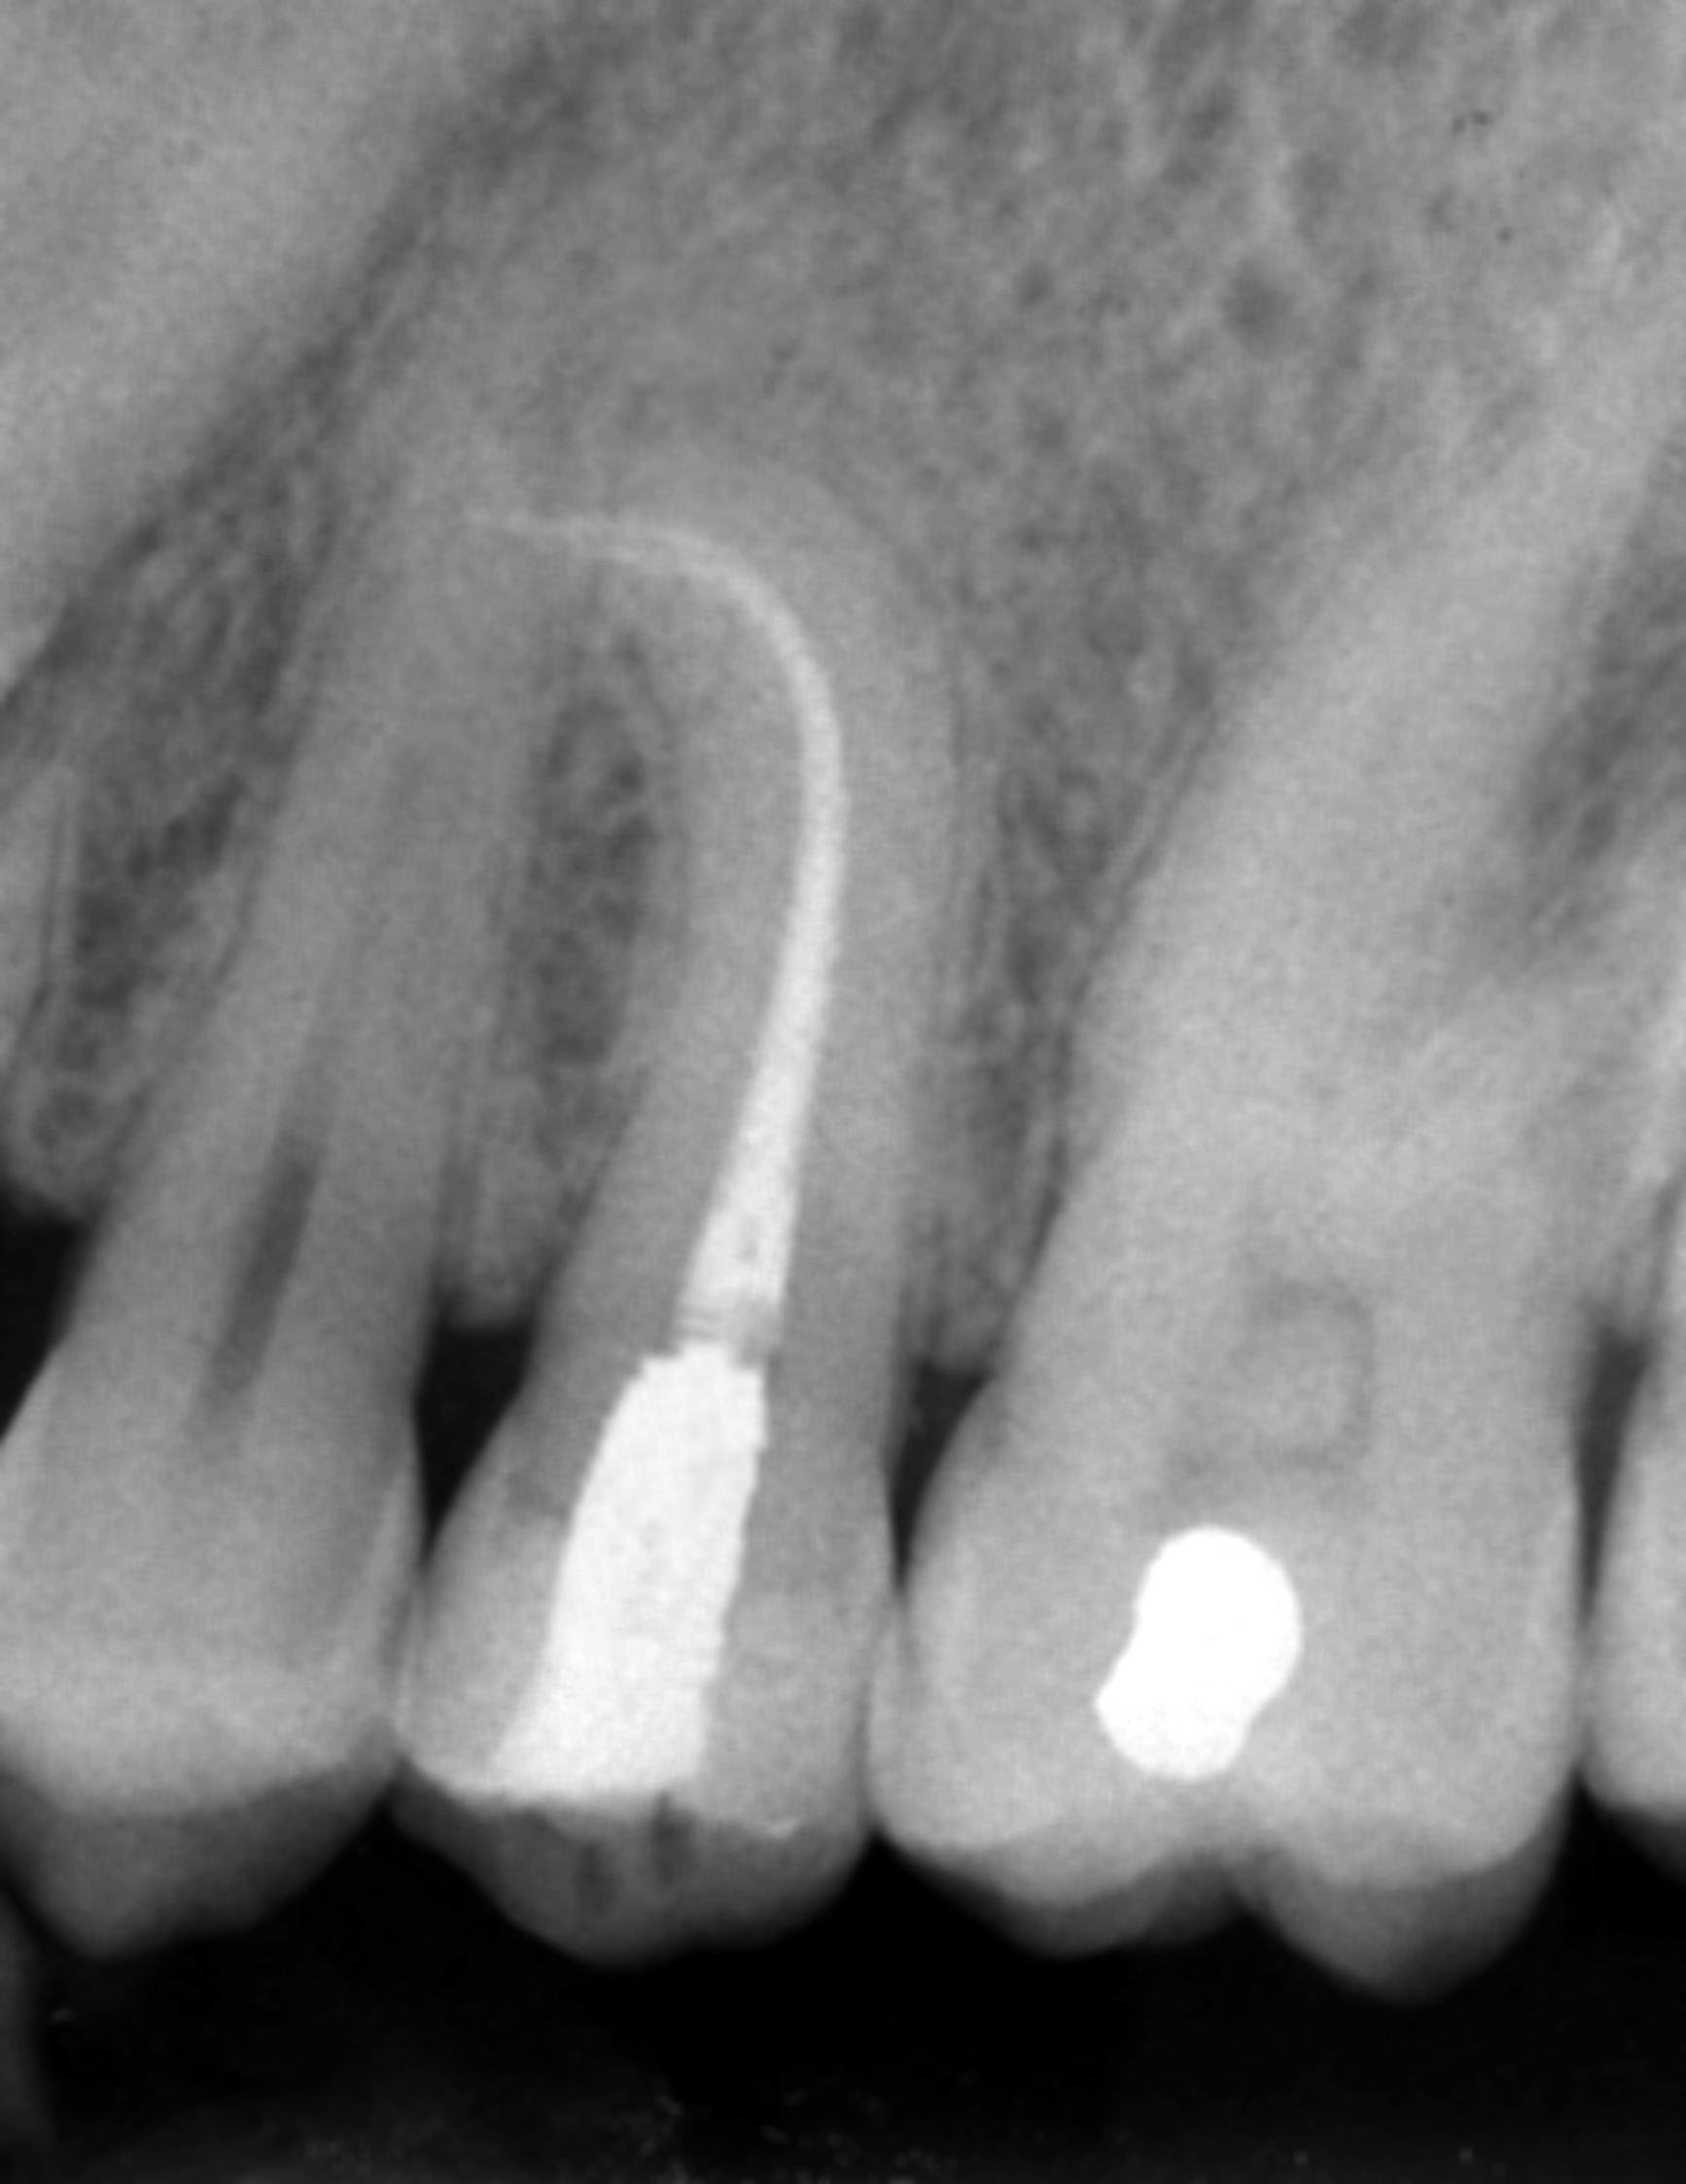

Apertura della corona fino ad arrivare alla camera pulpare (tale trattamento viene eseguito tramite anestesia locale). Si rimuove la polpa e si cercano i canali radicolari del dente, una volta trovati si estirpano i nervi. Si allargano e si puliscono i canali del dente, (tramite strumenti al Nichel titanio o strumenti manuali) prendendo anticipatamente le misure dei canali (per non uscire oltre apice). Si disinfettano i canali e si eseguono vari lavaggi tra un passaggio e un altro per elimininare il fango dentinale. Il medico a questo punto verifica la possibilità di chiudere definivamente i canali o lasciare il dente in prova, inserirendo nei canali un disinfettante e eseguendo una chiusura provvisoria. Al momento di chiudere il dente definivamente, questo viene preparato rieseguendo le misure dei canali da chiudere ed usando per la stessa lunghezza del canale, un cono di guttaperga del diametro necessario. Si scalda il cono in guttaperga e si inserisce nel canale. Durante il trattamento endodondico vengono effettuati una serie di esami radiografici per verificare i risultati, le lunghezze, la forma dei canali.

L'esame radiografico, fondamentale per porre diagnosi in odontoiatria, in endodonzia è irrinunciabile perché è l'unico strumento che ci permette di "vedere" all'interno della radice del dente, è quindi molto importante la possibilità di effettuare lastre con apparecchiature digitali che emettono un quarto della dose di raggi emessa da un radiografico tradizionale e che permettono di conservare la radiografia endorale in una cartella informatica del paziente senza possibili alterazioni nel tempo.